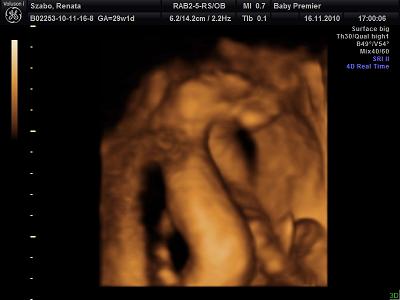

Itt mutatja hogy minden rendben mami!A lábacskája is látszik.

A lényeg hogy az arca elött nem csak a keze van hanem a lába is.